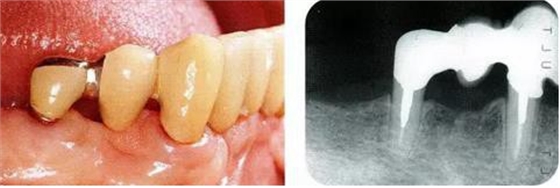

病例4維系鄰牙的骨水平的戰(zhàn)略性拔牙:

圖17-1 ( 左 ),2 ( 右 )▲右下4近中9mm的骨緣下缺損,兩側(cè)全口橋體修復(fù),但是這顆患牙保留的情況下會(huì)影響牙列的維持,鄰接牙的骨水平在較高的位置,拔牙后可以獲得平坦的骨水平。即使是右下4嘗試再生療法,假說(shuō)可以100%的成功,右下3遠(yuǎn)中骨水平也會(huì)形成3mm以上的臺(tái)階。而且再生治療也需要患者登上1年半以上的時(shí)間。所以最終選擇拔牙的處理。